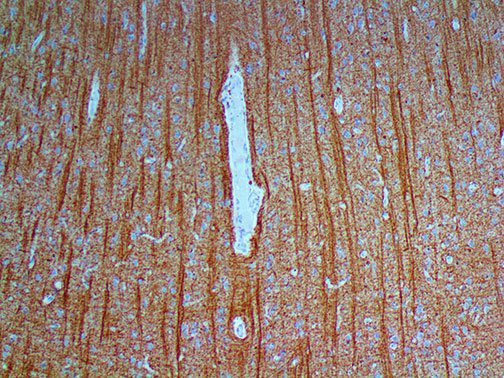

This activation induces inflammatory monocytes to highly express IL-6, starting a localized and then systemic cascade effect that results in hyperproduction of IL-6, which accelerates the inflammatory process. Because IL-6 also increases vascular permeability, excessive levels cause blood vessels to become very leaky. This, along with clotting factors released from vascular endothelial cells, stimulates the coagulation cascade, resulting in microthrombosis (tiny clots), which leads to ischemia and tissue death of the kidney, intestines, heart, liver, brain and extremities.